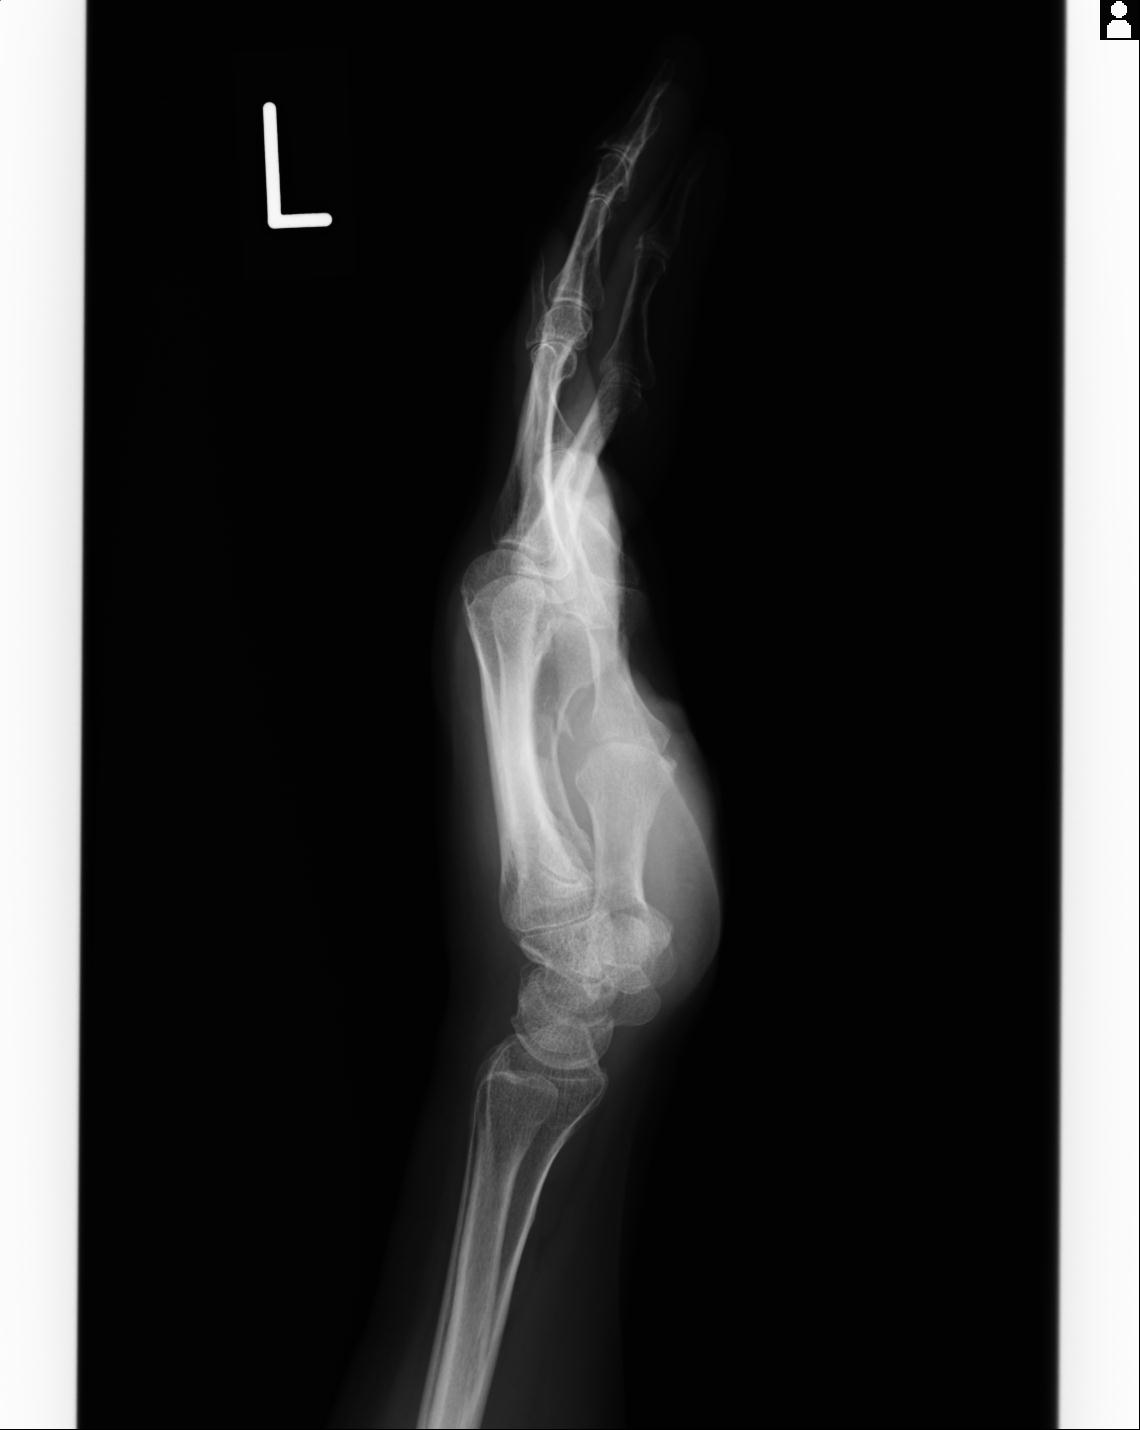

110211 1/6 1/8 左前腕 4R 15歳男性 橈骨骨幹部骨折